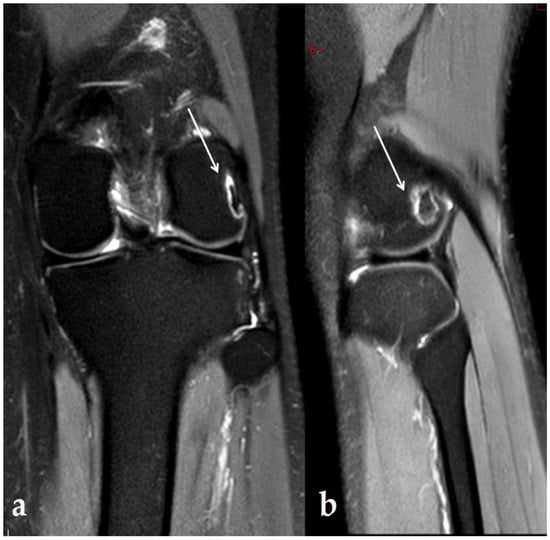

- Yeh, L.-R.; Chen, C.K.H.; Tsai, M.-Y.; Teng, H.-C.; Lin, K.-L. Focal Bone Abnormality as a Complication of Ultrasound Diathermy: A Report of Eight Cases. Radiology 2011, 260, 192–198. [Google Scholar] [CrossRef]

- Kim, S.J.J.; Kang, Y.; Kim, D.H.; Lim, J.Y.; Park, J.H.; Oh, J.H. Focal Bone Marrow Lesions: A Complication of Ultrasound Diathermy. Clin. Shoulder Elb. 2019, 22, 40–45. [Google Scholar] [CrossRef]